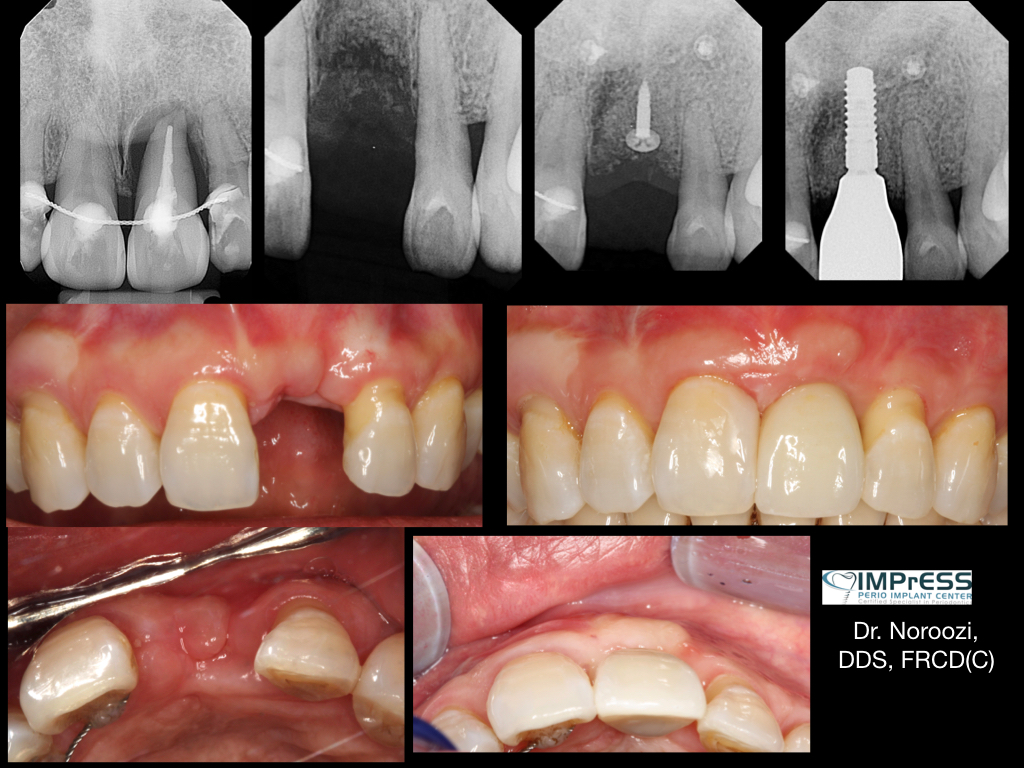

Before & Afters of Dental Implant Patients

Complete Dental Implant Cases Gallery

• Your specialist will carefully examine your mouth and take x-rays of your head, jaw, and teeth to find out if dental implants are right for you.

• During the first stage of surgery, your dentist or specialist will put a dental implant into your jawbone beneath the gum tissue. The gum tissue is then stitched back into place. As the tissue heals, the implant will bond with the bone and attach to the gum. It can take several months to heal.

• During the second stage of surgery and once the tissue is healed, your dentist or specialist will attach an abutment to the implant. An abutment is a post that connects the replacement tooth to the implant. In some cases, the first and second stage of implant surgery may be done in one single stage.

• An artificial replacement tooth is made and your dentist or specialist attaches it to the abutment. It may take several appointments to properly fit the replacement tooth to the abutment.

Dental implant treatment is sometimes a team effort between your periodontist and a restorative dentist.  Dr. Noroozi  at IMPrESS Perio Implant Center located in Burnaby BC performs the actual implant surgery, initial tooth extractions, and bone and gum grafting if necessary.  The restorative dentist (your dentist) or our specialists (if you do not have a dentist) will fit and make the permanent prosthesis. Your dentist or our specialists will also make any temporary prosthesis needed during the implant process.

General Disclaimer: The results in the photographs are examples only and do not imply any certainty of the result of a procedure, and all outcomes are subject to the circumstances of the individual patient.